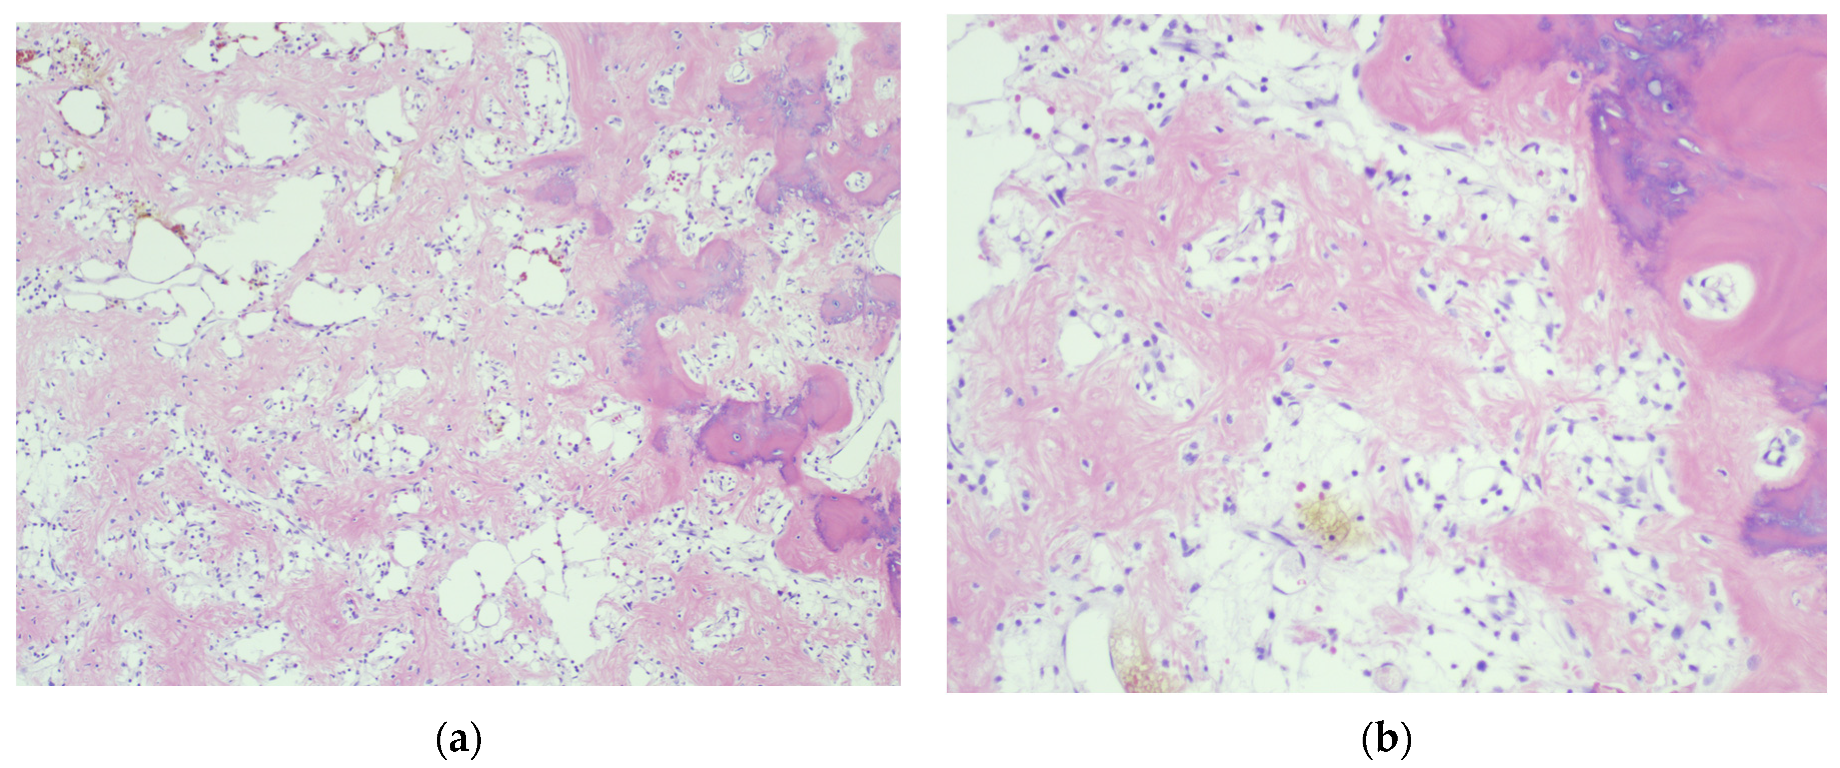

4.3. Final Diagnosis

4.5.3. Secondary Aneurysmal Bone Cysts